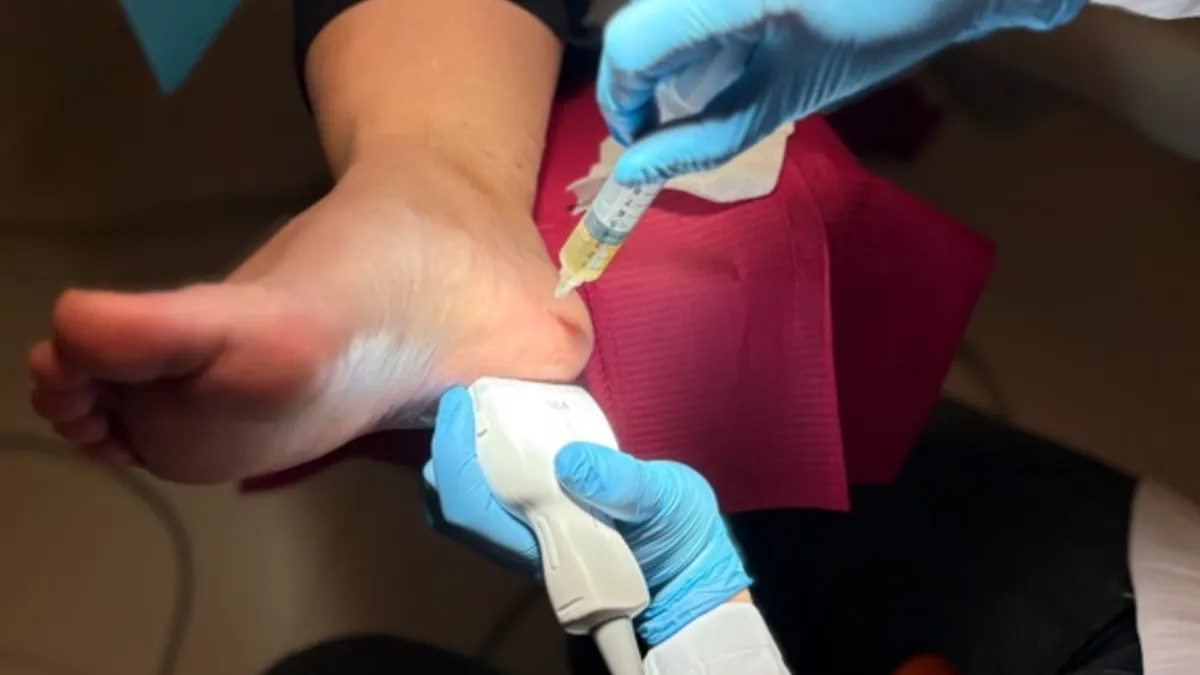

- Ecografía diagnóstica - Evaluación en tiempo real

Neuromodulación Percutánea Ecoguiada

También ofrecemos electrólisis percutánea para casos de fascitis plantar muy resistentes al tratamiento.

Infiltraciones Ecoguiadas

Infiltraciones ecoguiadas de precisión: corticoides, PRP, ácido hialurónico y biorreguladores para el tratamiento del dolor y la regeneración tisular.

Plasma Rico en Plaquetas (PRP)

Tratamiento regenerativo con plasma rico en plaquetas: factores de crecimiento del propio paciente aplicados bajo control ecográfico para tendinopatías, fasciopatías y artrosis del pie y tobillo.